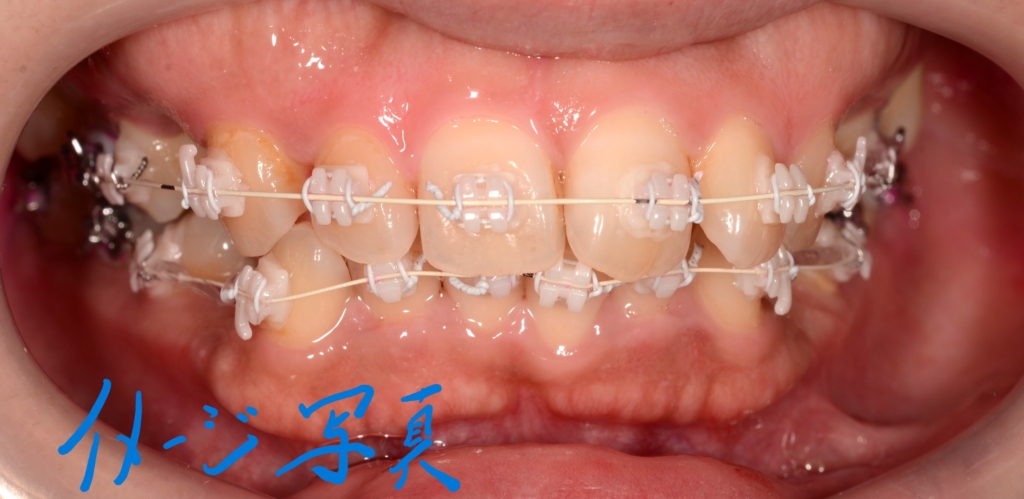

この方の写真が見つからないので、同じことをしている他の方の写真をイメージ写真としてあげています

上下とも前歯がきれいに並んで、引っ込めるステップに入る目途がついたので、上の奥歯辺りにアンカースクリューを植立しました。

上下とも前歯を後方へ最大限に引っ込めて行きます